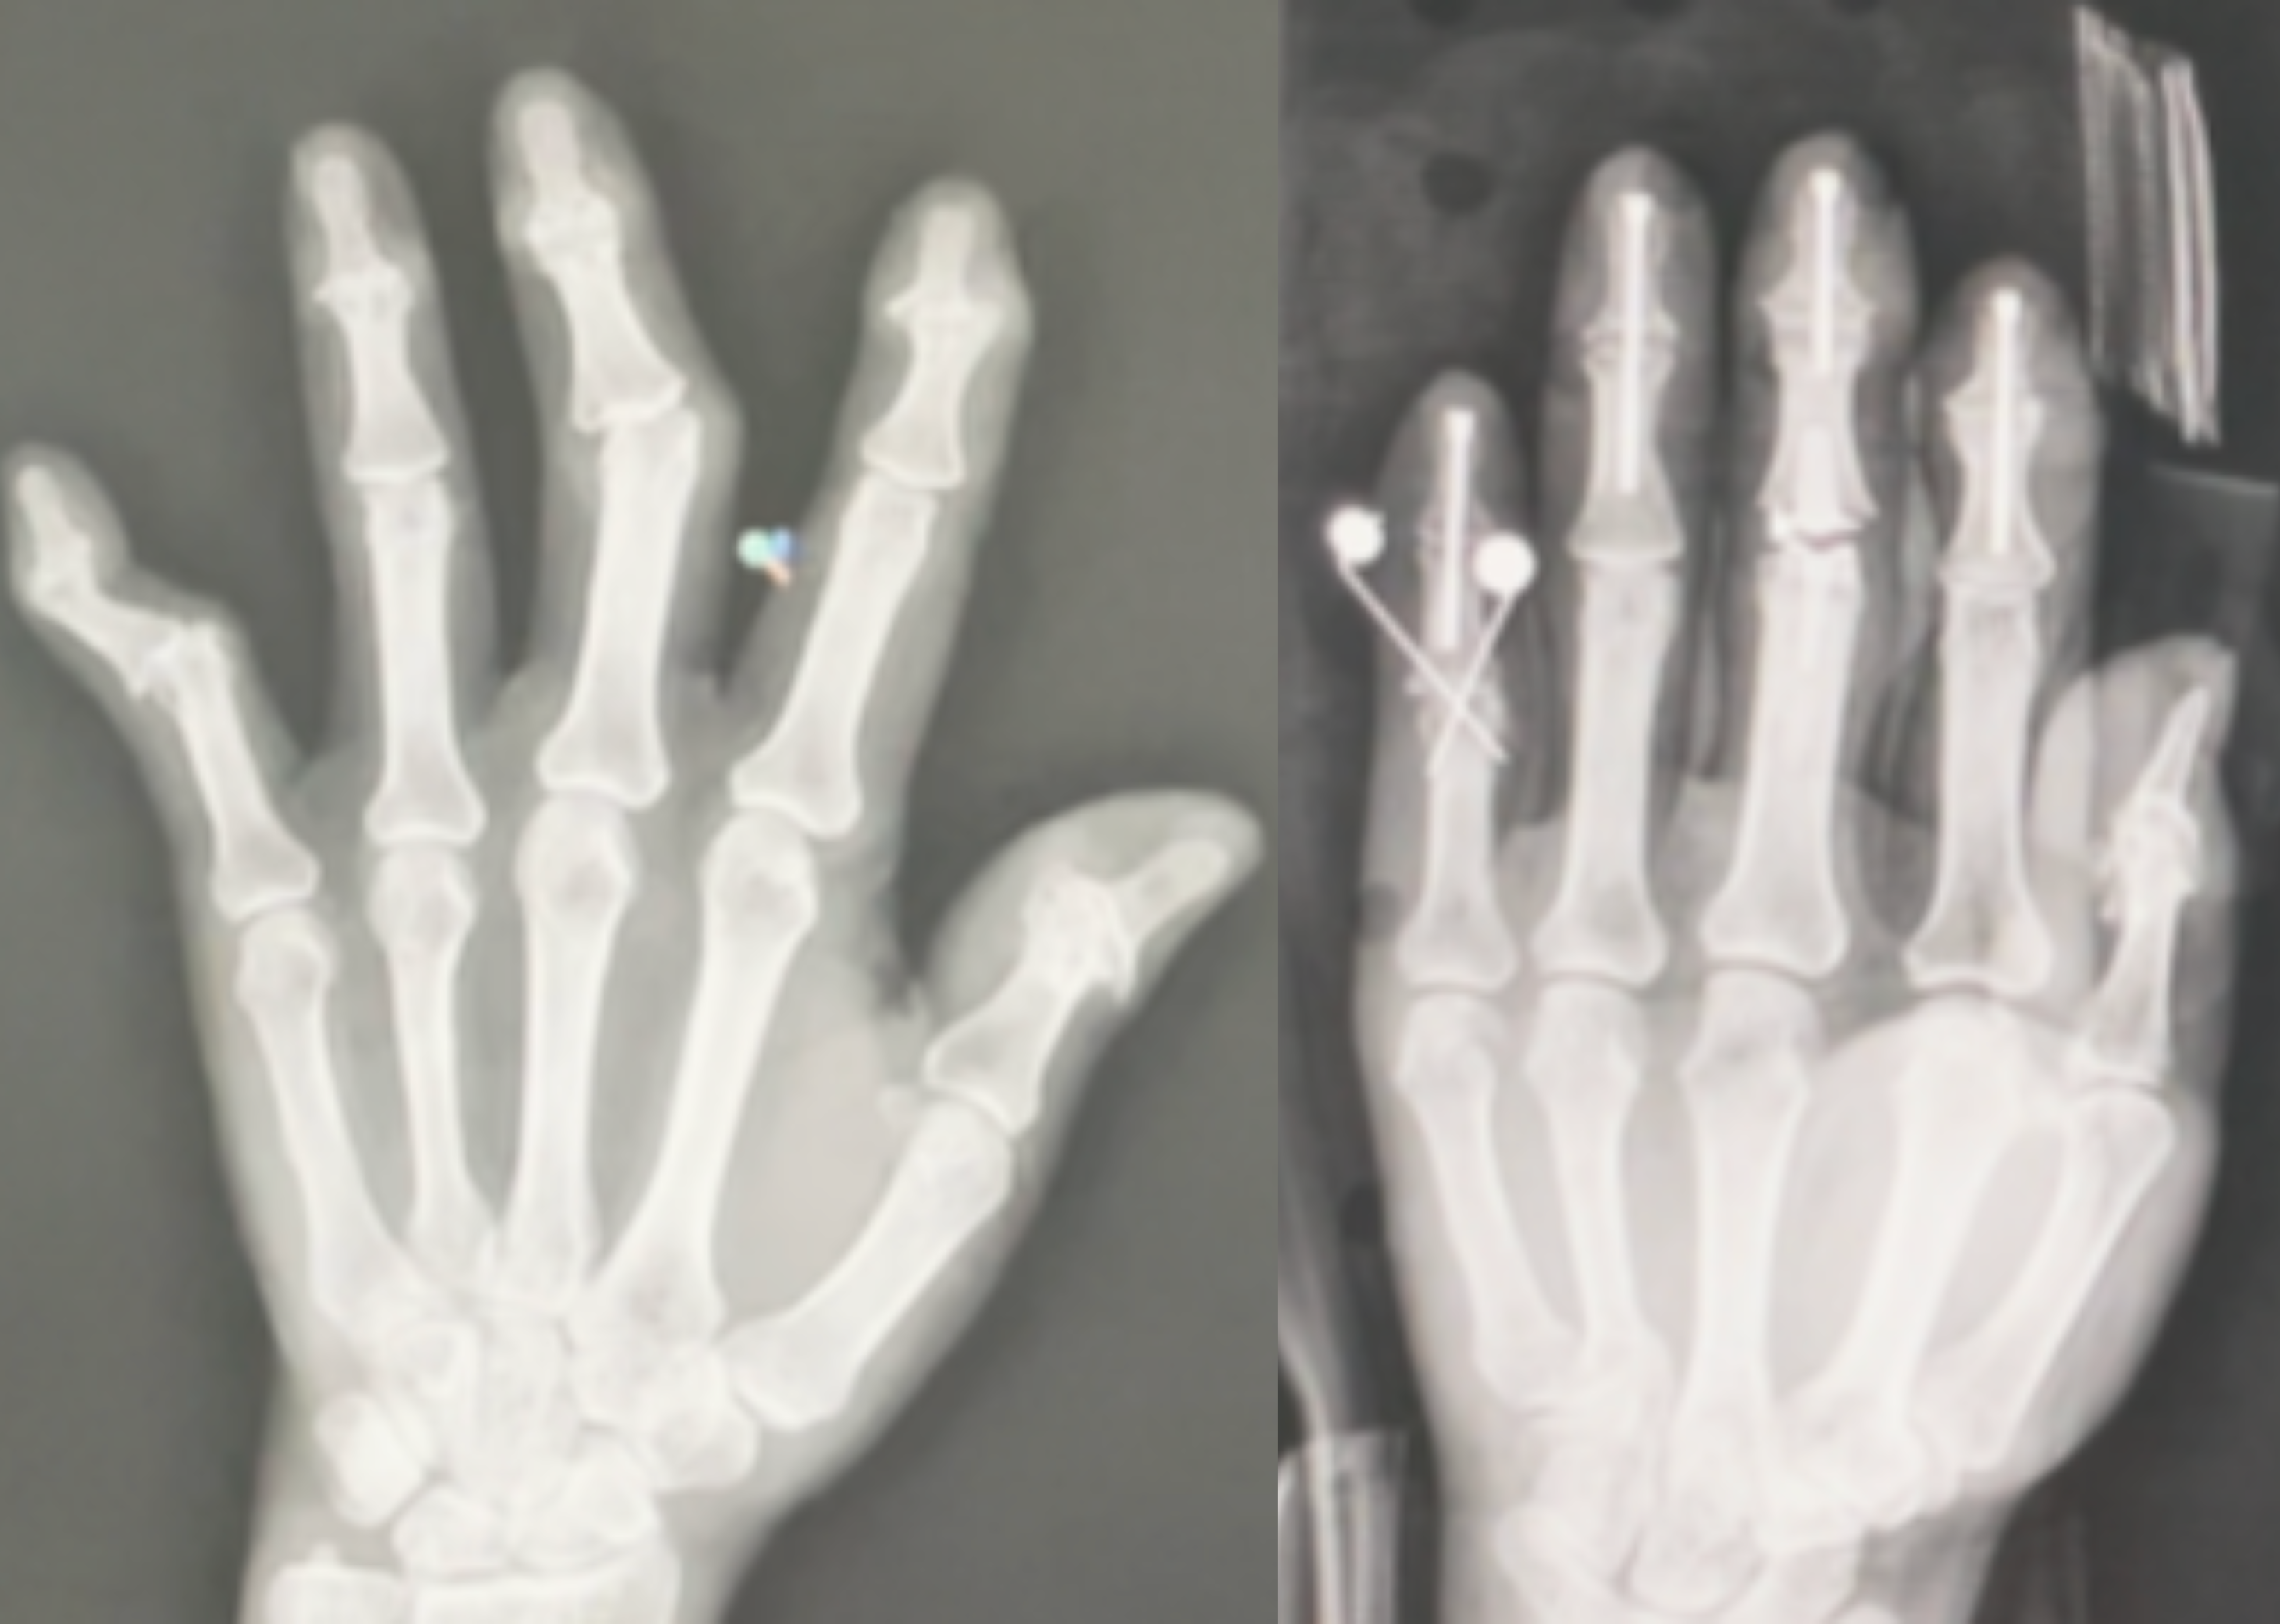

X-Ray Images: Before and After Treatment

My Fingers One Month After Surgery

My Fingers Six Months After Surgery

My Fingers Nine Months After Surgery